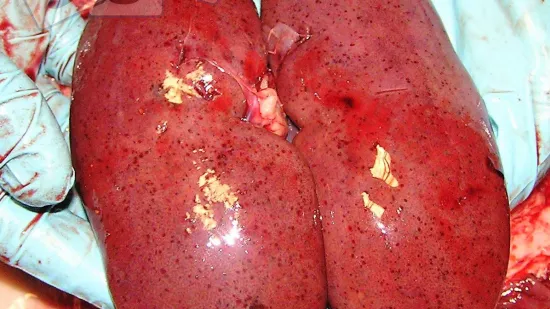

Ces rates de porcs de 100 kg de pids vif semblent :